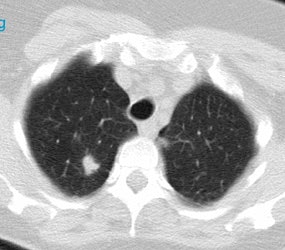

Positive lung cancer screening exam: The patient shown below had undergone lung screening CT in 2002 (left image). The patient was lost to follow-up, but returned for a repeat screening exam in 2007. The 2007 (right image) exam revealed a new stage I NSCLC in the right apex. There is a small linear scar in the medial left apex. |